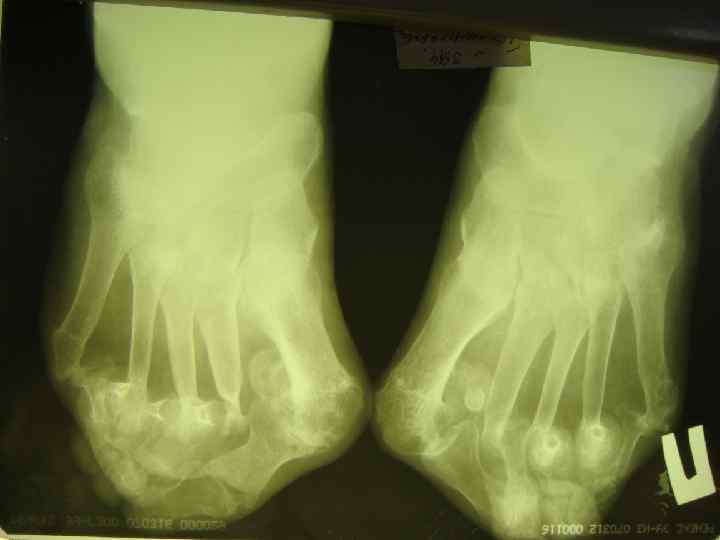

ДИАГНОСТИЧЕСКИЕ КРИТЕРИИ РА (АРА, 1987, 1998) l l l 5. НАЛИЧИЕ ПОДКОЖНЫХ УЗЛОВ В ОБЛАСТИ ЕСТЕСТВЕННЫХ КОСТНЫХ УТОЛЩЕНИЙ И РАЗГИБАТЕЛЬНЫХ ПОВЕРХНОСТЕЙ КОНЕЧНОСТЕЙ ИЛИ ПЕРИАРТИКУЛЯРНО (РЕВМАТОИДНЫЕ УЗЕЛКИ). 6. ОБНАРУЖЕНИЕ РЕВМАТОИДНОГО ФАКТОРА В СЫВОРОТКЕ КРОВИ ИЛИ СИНОВИАЛЬНОЙ ЖИДКОСТИ. 7. ТИПИЧНЫЕ РЕНТГЕНОЛОГИЧЕСКИЕ ИЗМЕНЕНИЯ: ОКОЛОСУСТАВНОЙ ОСТЕОПОРОЗ, ЭРОЗИВНЫЙ АРТРИТ.

R-ЛОГИЧЕСКИЕ СТАДИИ РА (STEINBROCKER, 1949) l СТАДИЯ I — ОКОЛОСУСТАВНОЙ ОСТЕОПОРОЗ БЕЗ l СТАДИЯ II — НЕЗНАЧИТЕЛЬНОЕ СУЖЕНИЕ l СТАДИЯ III — ЗНАЧИТЕЛЬНОЕ РАЗРУШЕНИЕ ХРЯЩА И l СТАДИЯ IV — ПРИЗНАКИ III СТАДИИ + АНКИЛОЗ ДЕСТРУКТИВНЫХ ИЗМЕНЕНИЙ. СУСТАВНОЙ ЩЕЛИ, ЕДИНИЧНЫЕ УЗУРЫ КОСТЕЙ. КОСТИ: ВЫРАЖЕННОЕ СУЖЕНИЕ СУСТАВНОЙ ЩЕЛИ, МНОЖЕСТВЕННЫЕ УЗУРЫ, ПОДВЫВИХИ, КОСТНЫЕ КИСТЫ.